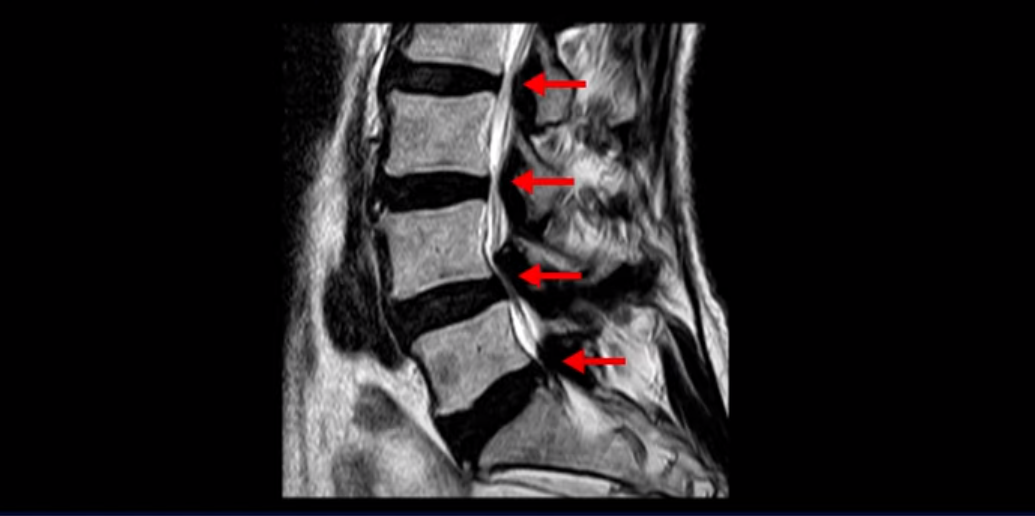

이분 MRI를 보면 허리 여러 마디가 퇴행되어 있고 여러 군데 협착이 있는데

특히 4번 5번 마디의 척추관협착 즉, 중심성 협착은 너무나도 심해 보입니다.

아예 신경이 거의 보이지 않을 정도입니다. 이 정도로 협착이 심하니까 수술 밖에는 방법이 없다고 얘기를 듣고 증상도 매우 심합니다. 양쪽 엉덩이부터 다리 발바닥까지 아프고 다리의 감각이 떨어지고 시린 증상이 있습니다. 걸을 때 마비가 오면 슬리퍼가 벗겨져도 모른다고 하셨고 잠도 제대로 못 자는 상태였습니다. 그런데 이렇게 협착이 심해 보이고 증상도 심한 환자분을 어떻게 수술 없이 치료 가능한 걸까요? 지금부터 설명해 드립니다.